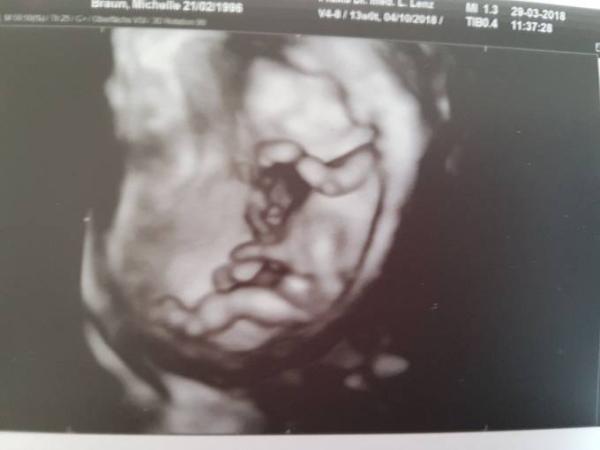

Guten Morgen ihr Lieben Ich bin heute bei 13+4 und habe am Donnerstag den Termin zur nackenfaltenmessung. Das Kind ist letzte Woche Freitag 3 Tage kleiner als laut Kalender gewesen. Meine eigentliche Frage ist: wann hattet ihr euer outing ob Team rosa oder blau?

Bild zu Outing welches Team? - Schwanger - wer noch? Rund um die Schwangerschaft